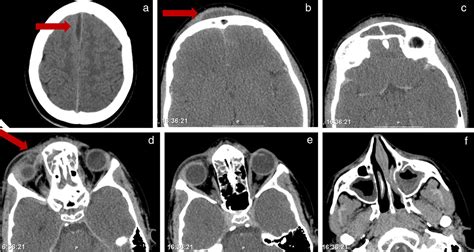

Diagnosis of Pott's Puffy Tumour relies heavily on advanced medical imaging. Physical examination is insufficient to determine the depth of the bone involvement or the presence of intracranial complications. Radiologists and surgeons work in tandem to evaluate the extent of the disease.

Computed Tomography (CT) To visualize bone erosion, sinus opacification, and subperiosteal abscess.

Magnetic Resonance Imaging (MRI) To detect intracranial complications, such as epidural abscess or venous sinus thrombosis.

At its core, Pott's Puffy Tumour is not a true neoplasm or tumor in the oncological sense, but rather a clinical presentation of an osteomyelitis of the frontal bone. It is almost always secondary to untreated or inadequately treated frontal sinusitis or direct trauma to the forehead. The infection spreads from the frontal sinus into the marrow space of the frontal bone, creating a localized collection of pus—an abscess—beneath the periosteum. This causes the classic "puffy" appearance on the patient's forehead.

The progression of the condition can be rapid. Because the bone is porous, the infection can easily penetrate the inner table of the skull, leading to an intracranial abscess or meningitis. Understanding this mechanism is crucial because the superficial swelling is often just the "tip of the iceberg" regarding the extent of the infection inside the cranium.